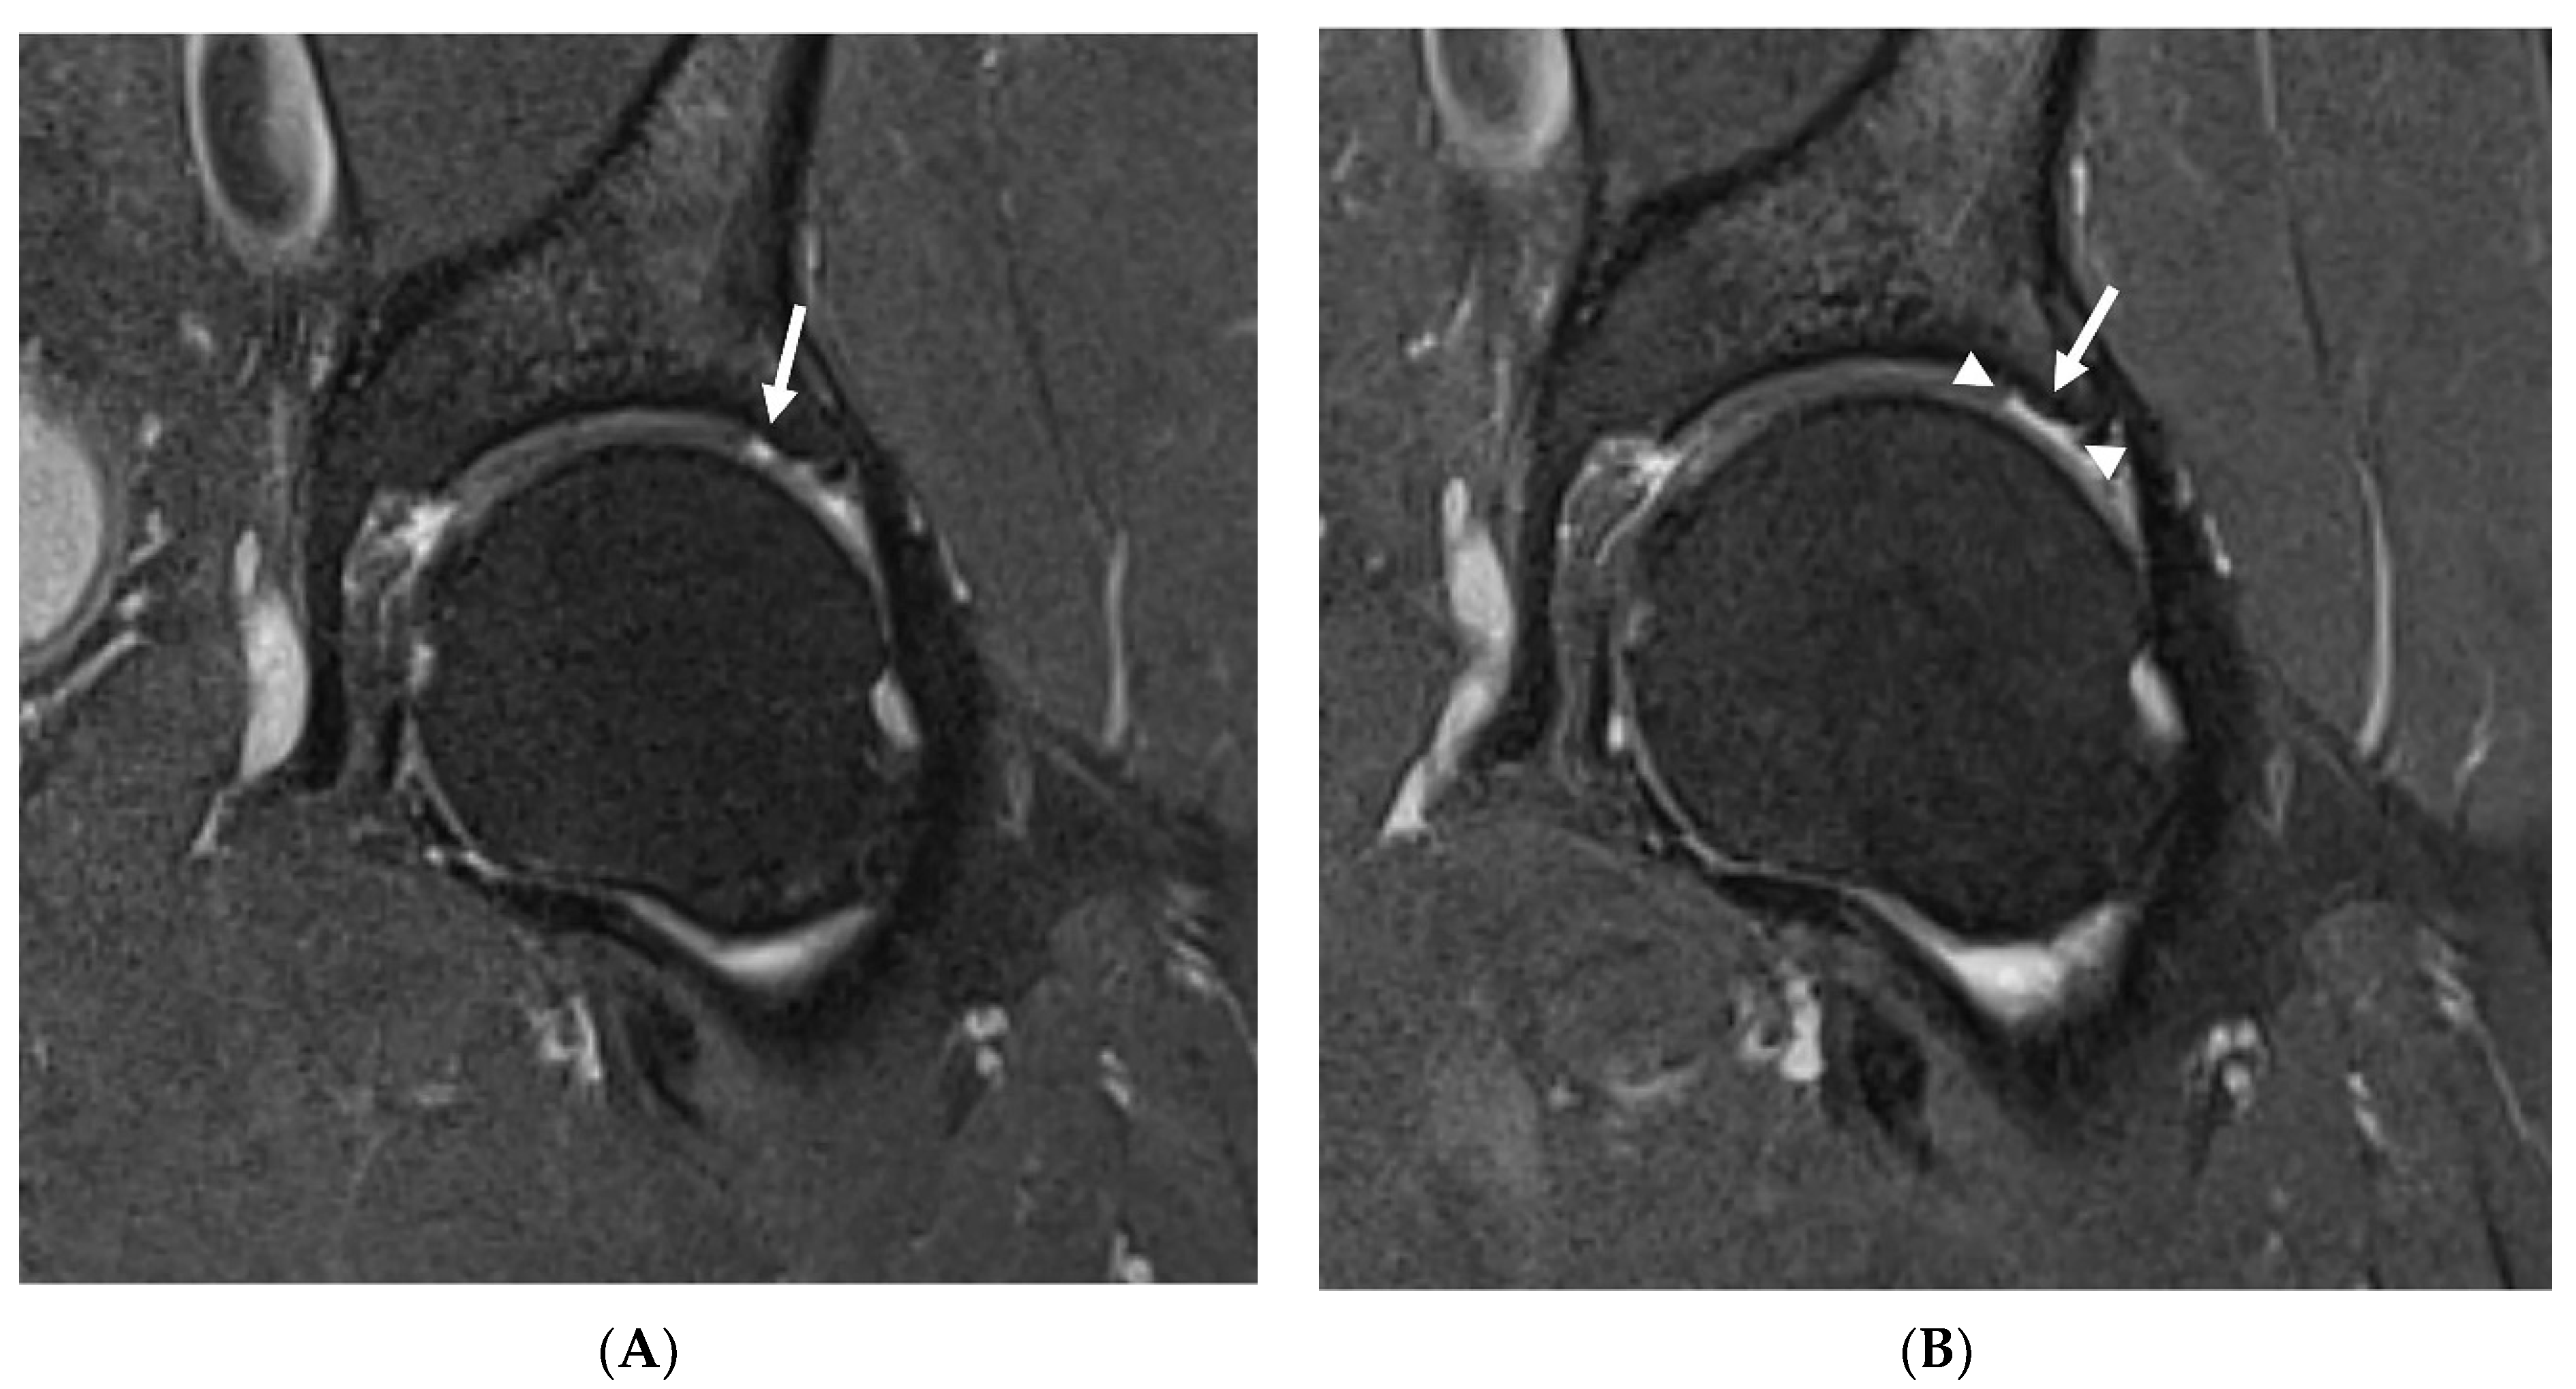

In the study group, no statistically significant changes in any of SHORMI subscales were observed during the 12-month follow-up. However, on an individual basis, two patients showed a progression of cartilage defects reflected by a change in the SHORMI score from 1 to 2, and one patient showed a progression of subchondral cysts similarly reflected by an increase in the SHORMI score. In three patients, enlargement of cartilage defect area was observed; however, since those were already full-thickness defects, it did not affect SHORMI score (Figure 1); in one of those patients the area of bone marrow edema increased as well. In one patient, the paralabral cyst increased substantially. All of those patients (n = 7) were labeled “progressors”, in contrast to the remaining patients (n = 17) that showed no change in MRI (“non-progressors”) (Table 5). This division was subsequently used in further analysis.

Figure 1.

Progression of chondral defects missed by SHOMRI. Baseline MRI (A) showing a full thickness cartilage defect (arrow) corresponding to SHOMRI grade 2 in a superolateral acetabular region in a 60-year-old patient. In a follow-up study (B), the defect covers a larger area (arrowheads show the margins of the defect), which still corresponds to SHOMRI grade 2.